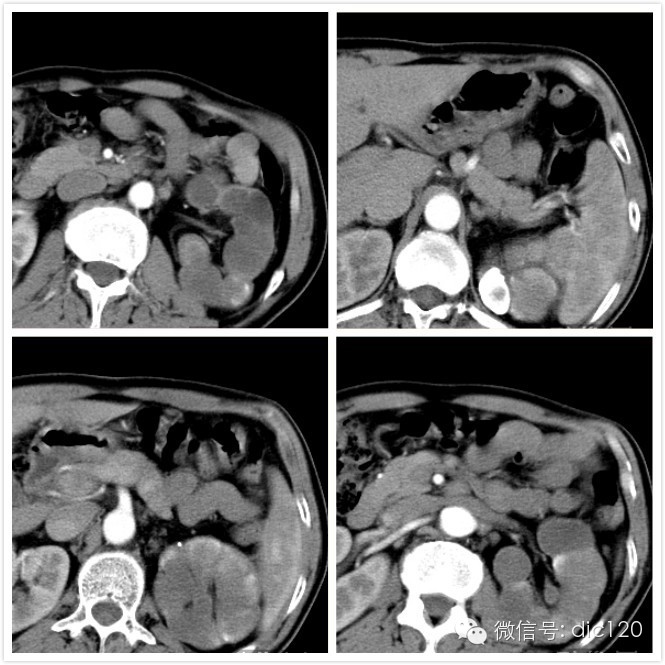

【影像图片】CT平扫图像:

CT图像特点:左侧肾盏、肾盂扩张,呈多发囊性低密度灶,囊内CT值略高于水;肾脏实质萎缩。 病变内可见结节状、云絮样子钙化灶,增强后未见明显强化。

结果:左侧肾脏结核,右肾多发囊肿